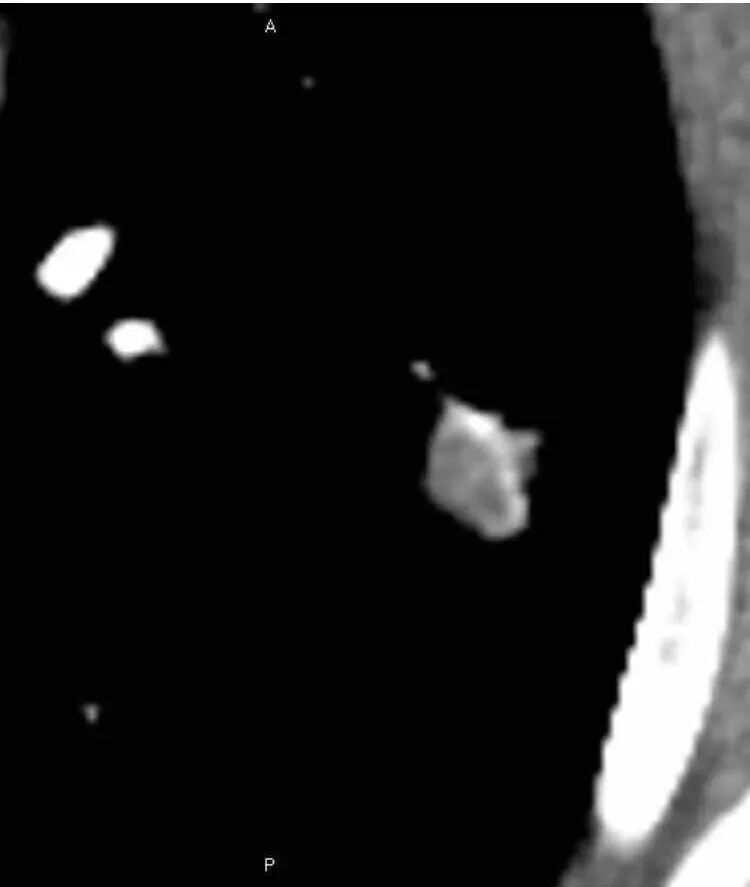

女,50。实性不规则结节,大小12*13mm,分叶、毛刺、胸膜凹陷,牵拉力强,增强渐进性强化,动脉期强化20,静脉期还有进一步强化。边缘强化,点状坏死。

其内血管被破坏。

女性,50岁。U型凹陷、平直征

南边:支持炎性

1.胸膜下略不规则实性密度结节影,孤立,缺乏典型深分叶,可见淡薄边界模糊磨玻璃晕,可见相对细长软毛刺。

2.如南边老师分析,病灶缺乏边缘膨隆优势,甚至部分平直内收。

3.病灶收缩力不强,整体强化程度不显著。

4.综上,病灶更符合炎性,如隐球菌感染等,而不大符合肺腺癌。具体到机化性肺炎略有些出乎预料。